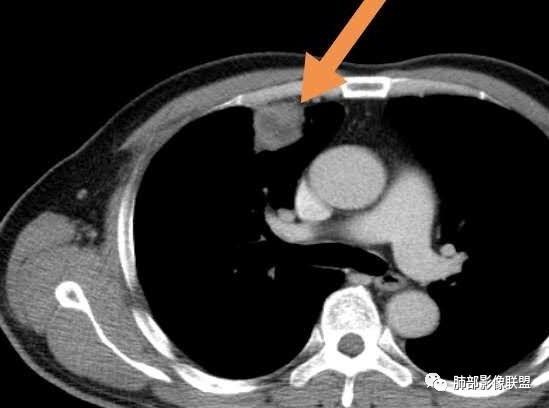

甄德强:这个是炎症,治疗一月后复查图片。

回顾性分析本病例,小编觉得鉴别诊断聚焦于肺鳞癌和炎性病灶(包括结核)之间,这个病灶的炎性征象大于恶性征象;以下是这个病例的的炎性征象:①病灶边缘平直收缩为主,也缺少典型的分叶毛刺;②支气管走行于病灶中央截断,断端比较圆钝;③近端引流支气管壁增厚;④整体强化不显著,坏死区太圆太规整,边缘隐约显示强化的环;⑤血管走形自然,未见明显破坏征象;⑥胸膜外脂肪间隙增宽,胸膜广基地增厚,未见栽赃;⑥52岁偏年轻(此条也不大支持鳞癌)

虽然本例患者支气管截断,病灶中央截断炎性及恶性都可以,断端向病灶一侧圆钝更支持炎性。